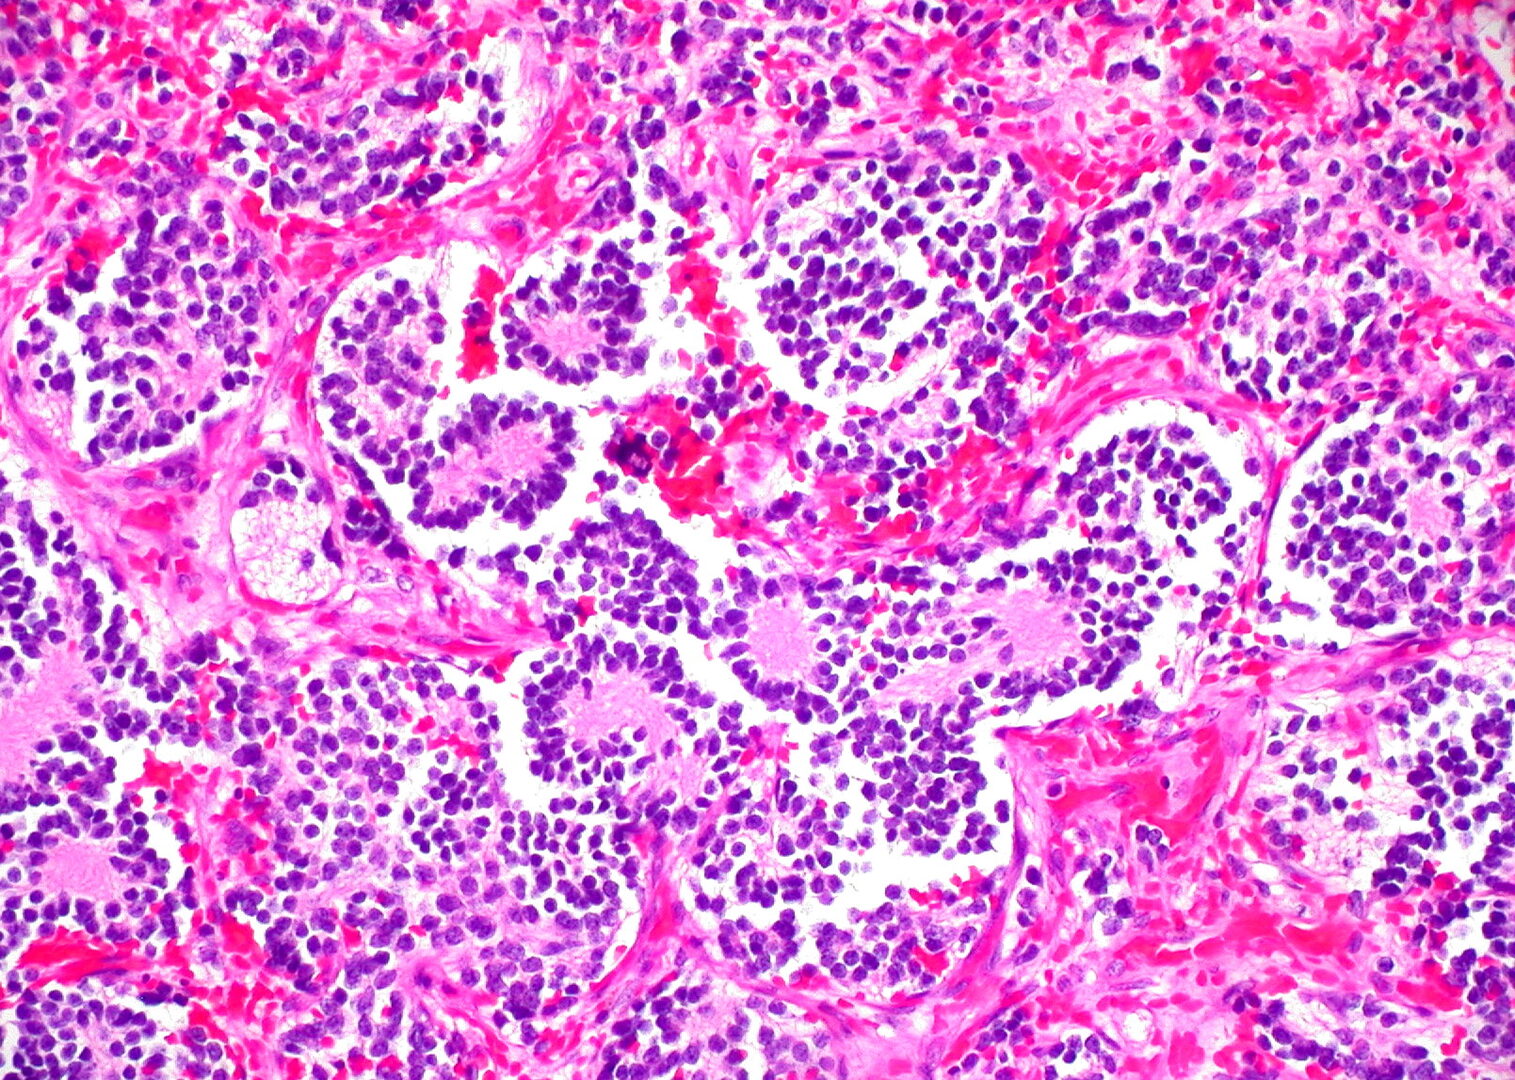

El neuroblastoma es un tipo de tumor sólido poco frecuente que suele afectar a niños y es una enfermedad difícil de tratar, con altas tasas de recaída a pesar del tratamiento. El equipo del Baylor College, liderado por Helen Heslop, llevó a cabo un ensayo clínico de fase 1 con 19 niños con neuroblastoma, entre 2004 y 2009, en el que probaron células T modificadas para reconocer GD2, una proteína con altos niveles de expresión en el neuroblastoma.